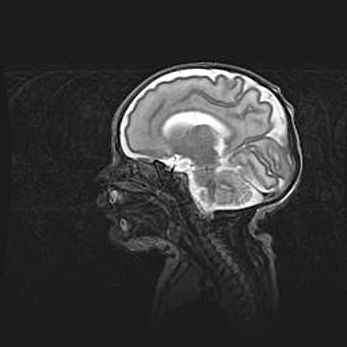

Ниже представлена  галерея МРТ снимков, полученных с применением LMT неонатальных матричных РЧ катушек. Также каждая группа МРТ снимков сопровождается информацией о пациенте (диагноз, возраст, вес, пол, срок гестации) и краткой сопроводительной расшифровкой диагноза.

Аномалия Денди-Уокера. Признаки гипоплазии мозолистого тела.

Возраст: 5 месяцев 3 дня

Вес: 5550 г

Пол: мужской

Окружность головы: 39 см

Срок гестации: 40 недель

Аномалия Денди-Уокера – это порок развития головного мозга, для которого характерна триада симптомов: гипотрофия или аплазия червя мозжечка и/или полушарий мозжечка, расширение четвёртого желудочка с формированием ликворной кисты задней черепной ямки, гипертензионная гидроцефалия различной степени.

Гипоплазия мозолистого тела относится к дефектам внутриутробного этапа развития мозговой ткани, возникающим в процессе закладки структур головного мозга, что происходит на начальных этапах развития эмбриона.